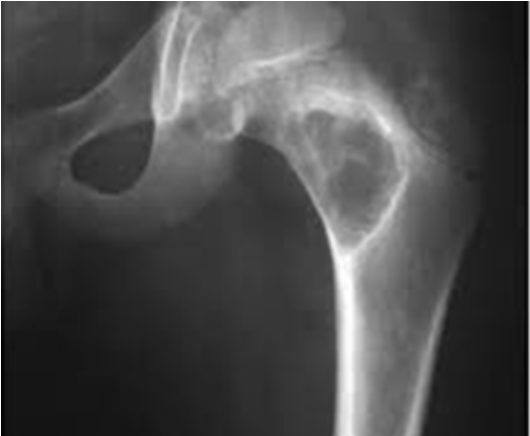

В ортопедии и травматологии рентгенологическое исследование используют для диагностики деформирующего коксартроза, артритов, асептического некроза головки бедренной кости, костных новообразований, вывихов, переломов шейки бедра и т. д. Рентгтенография позволяет подтвердить наличие патологии, но не всегда дает достаточно информации. Нельзя, например, получить послойное изображение тканей, из-за чего врачи не могут определить точную локализацию патологических изменений.

- сужение суставной щели. Признак дистрофических изменений суставных хрящей. Этот симптом выявляют у больных с деформирующим остеоартрозом и хроническими артритами;

- остеопороз. Снижение плотности костей. Характеризуется уменьшением количества костных балок в единице объема костной ткани. Патология развивается в пожилом возрасте. Сам остеопороз протекает бессимптомно, но на его фоне зачастую развивается деформирующий остеоартроз и переломы шейки бедра;

- деструкция. Возникает вследствие инфекционного процесса. Характеризуется разрушением участков кости с их дальнейшим замещением гноем, грануляциями или опухолевой тканью. Наличие деструкции может указывать на парапротезную инфекцию, остеомиелит, злокачественные новообразования;

- некроз. Неинфекционное омертвение костной ткани. Чаще всего участки некроза появляются в области головки бедренной кости. Причина – возрастное ухудшение кровотока и обмена веществ.

Выявление того или иного признака на рентгенограмме косвенно указывает на определенную патологию. Часто для постановки диагноза врачу хватает данных анамнеза, осмотра и рентгенографического исследования.